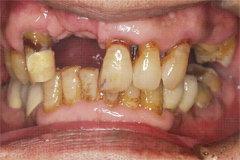

吉本歯科医院では、口内写真とパノラマレントゲンを撮影し、まずは顎の骨の状態まで詳しく確認しました。

(写真(1))虫歯の進行により歯の根っこに膿ができ、歯の周辺の骨まで溶け出している

・虫歯の進行により、歯の根っこに膿ができ、歯の周辺の骨までごっそり溶けてしまい歯がグラグラと揺れだした。

・親知らずを放置していたことにより、健全な歯を横に押し出し全体の噛み合わせ(咬み合わせ)のバランスを崩し、歯並びが悪く、不自然な力で噛み続けていたため歯が揺れだした。